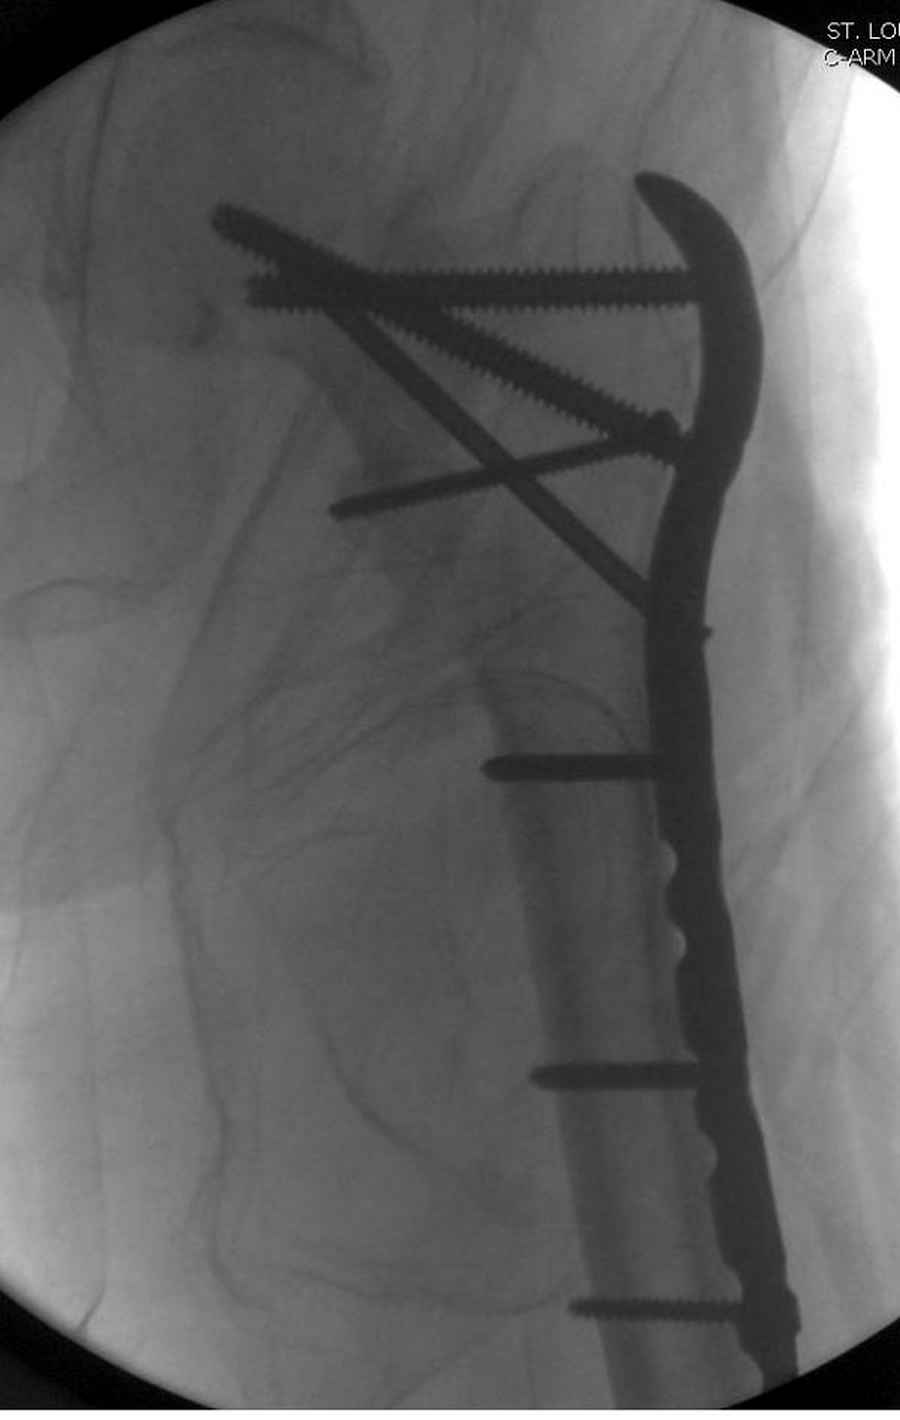

Из фиксаторов, мы бы применили цефаломедуллярные, потому что они "по закону моментов" из-за короткого рычага от центра головки к диафизу и по принципу "головка диафиз" механически лучше выдерживают нагрузки, чем пластины.

Но современные пластины с угловой стабильностью не отстают от медуллярных конструкций. Межфрагментарные шурупы и имплант как нейтрализирующее создаст адекватную фиксацию.

Здесь пара случаев фиксации похожих переломов:

первая высокоэнергетическая травма 36 лет